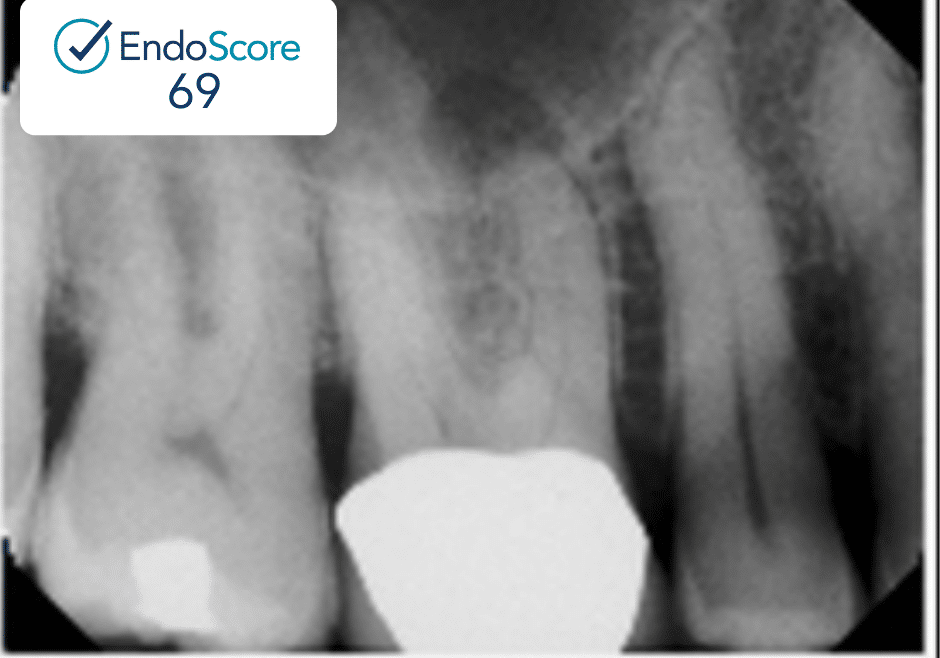

Case Study by Dr. Justin Kolnick

Endoscore of 69 was reduced to a final score of Endoscore 1 after MB2 canal was located and treated.

Obturated with EndoCeramicâ„¢ Sealer (Endo Direct) and single cone gutta percha.

EndoScore: 69 to 1